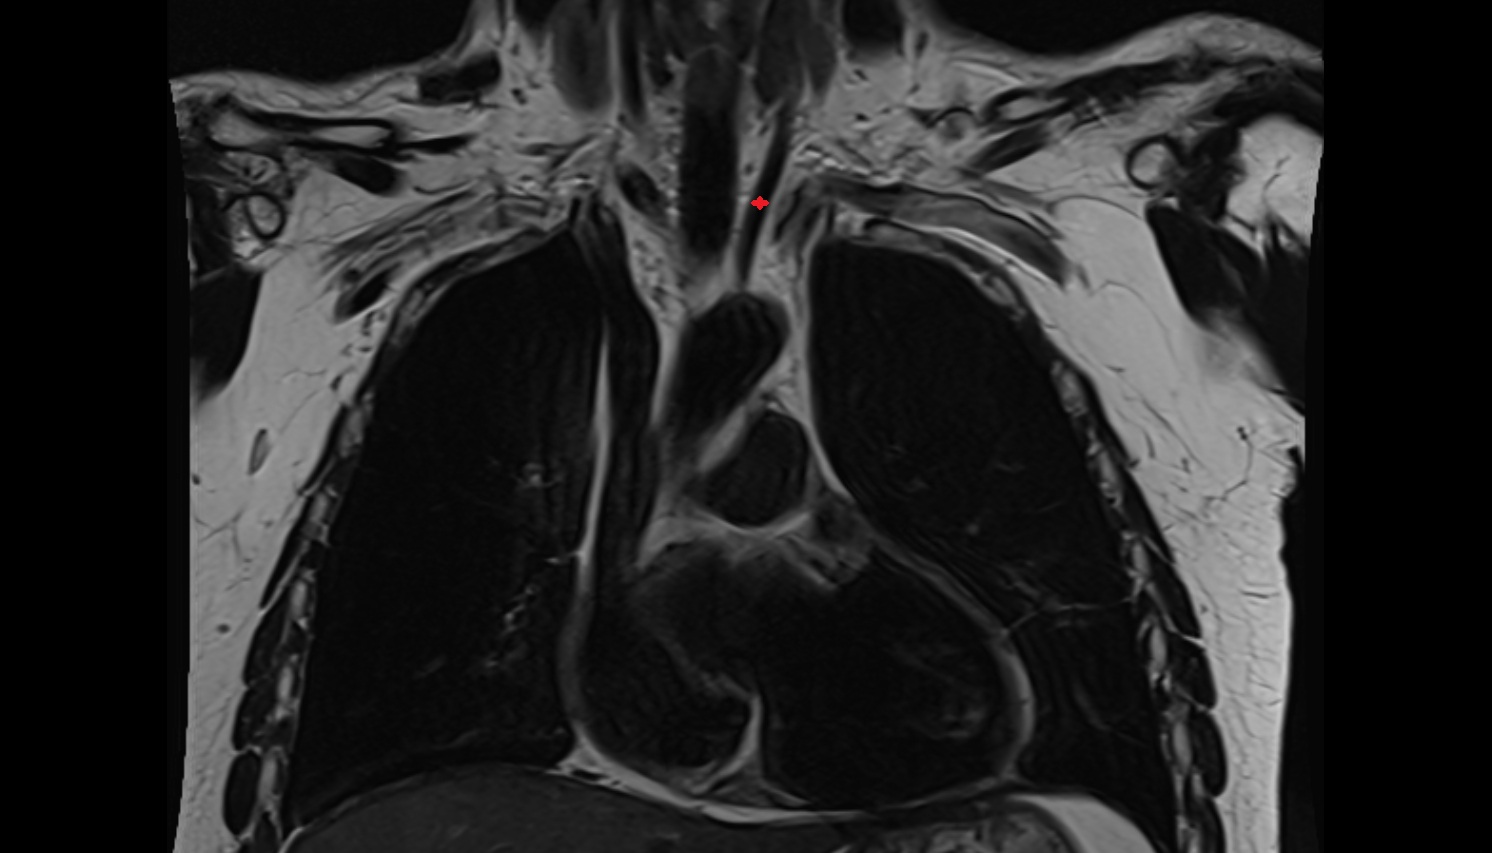

- Brachiocephalic trunk

- Common carotid artery

- Subclavian artery

- Trachea

- Thyroid gland

- Ascending aorta

- Arch of aorta